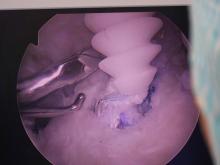

V Ortopedski bolnišnici Valdoltra smo pred kratkim gostili na strokovnem izobraževanju predsednika bolgarskega združenja za artroskopijo in športno travmatologijo. Izobraževanje je potekalo s poudarkom na rekonstrukciji anterolateralnega ligamenta, zadnje križne vezi, posterolateralnega kompleksa, različnih rekonstrukcijah ACL in operacijah ramena. Z dr. Robertom Halvadjianom smo ob zaključku izobraževanja opravili krajši intervju.

Izobraževanje je bilo z eno besedo izvrstno. Nivo je bil zelo visok. Po tej plati moram ponovno izraziti zahvalo in pohvalo mag. Bogdanu Ambrožiču, ki je prikazal nove operacijske pristope na optimalno izbranih pacientih. Pri vseh operacijskih posegih, nekatere smo izvedli skupaj, sem pridobil veliko znanja v smislu drobnih detajlov in optimizacije. Šlo je za specifične zadeve, ki jih z novimi tehničnimi pristopi rešujemo bolj optimalno kot na klasičen način. Zelo sem vesel, da sem imel priložnost vse to spoznati in osvojiti.

V prvi vrsti gre za skrbno izbrane operacije, kjer sem pri vsaki spoznal veliko drobnih, a v smislu končnega rezultata izjemno pomembnih napotkov in »malih skrivnosti« velikih mojstrov. Šlo je za veliko detajlov. Izvedene operacijske posege sicer dobro poznam in jih pogosto izvajam, a jih bom s pridobljenimi veščinami, triki in finimi dodelavami gotovo izvajal v prihodnje še bolj uspešno in kakovostno. Hkrati bi dodal, da sem bil pozitivno presenečen nad visoko profesionalnostjo celotnega bolnišničnega kadra, kar velja v enaki meri za zdravnike in ostalo zdravstveno osebje.

Brez dvoma bo to manj agresiven način operacije zadnje križne vezi. V tem primeru gre za pogost poseg, ki ga bom sedaj opravljal na bolj dodelan način. Podobno velja za operacijo anterolateralnega ligamenta, kjer gre za veliko novost, ki jo v OBV zelo dobro poznate.

Z Robertom sva se spoznala oktobra lani, ko je v Sofiji organiziral Balkanski artroskopski kongres. Na kongresu sem kot vabljeni predavatelj predstavil naše (Valdoltrske ) izkušnje pri zdravljenju različnih poškodb kolenskih vezi. Še posebej je bilo izpostavljena artroskopska kirurška tehnika rekonstrukcije zadnje križne vezi in posterolateralnega kompleksa. Poleg tega sem predstavil naše izkušnje z rekonstrukcijo anterolateralnega ligamenta, katerega smo v Valdoltri maja lani opravili med prvimi v Evropi. Na podlagi predavanja in nadalnjih najinih pogovorov sva se dogovorila o sodelovanju tudi na praktičnem nivoju in izrazil je željo, da osebno prisostvuje kompleksnim artroskopskim operativnim posegom na kolenu in ramenu. Kar se je tudi zgodilo. V omenjenem času (ko je bil pri nas) smo na različnih bolnikih opravili številne zahtevne rekonstruktivne posege na kolenu in ramenu. Na ta način smo lahko pokazali, kako v Valdoltri na sodoben in miniinvaziven način zdravimo tudi najtežje poškodbe.